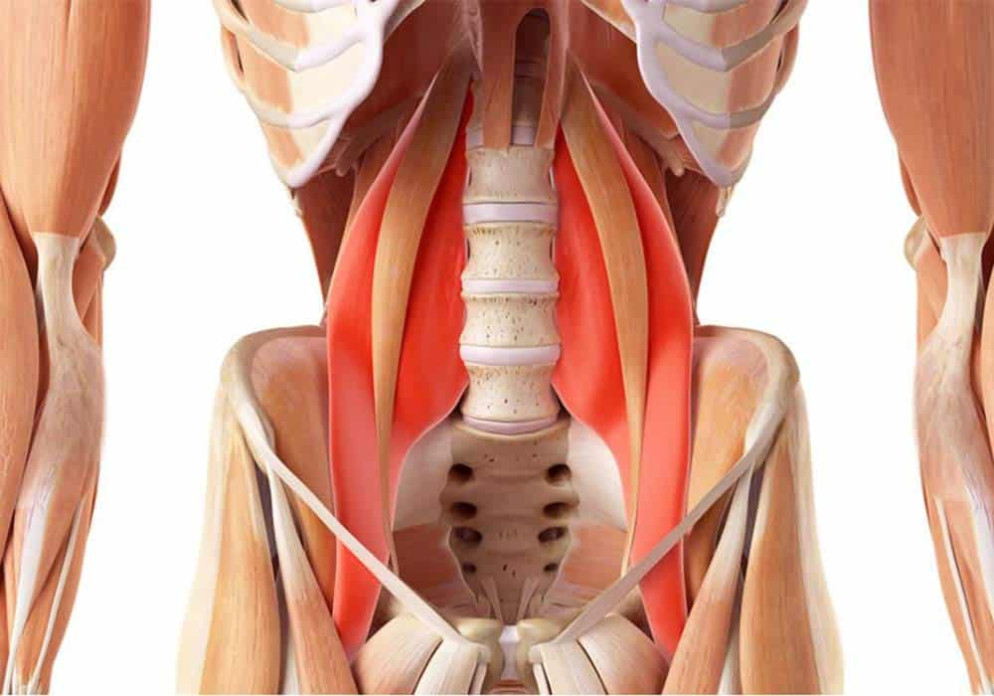

Cos’è il muscolo psoas?

Il muscolo psoas, formalmente chiamato psoas major, è un muscolo centrale molto importante. Lo psoas va dalle vertebre lombari al trocantere minore, vicino alla testa del femore.

Il muscolo psoas è spesso raggruppato insieme al muscolo iliaco e insieme sono indicati come iliopsoas. A causa della sua posizione in profondità nel nucleo del corpo, lo psoas è difficile da sentire con le mani e da percepire internamente.

A causa delle sue inserzioni sulle vertebre lombari, il muscolo psoas contribuisce all’inclinazione laterale del bacino (muovendo i fianchi uno alla volta) e alla flessione laterale della colonna vertebrale (portando la colonna vertebrale su un lato).